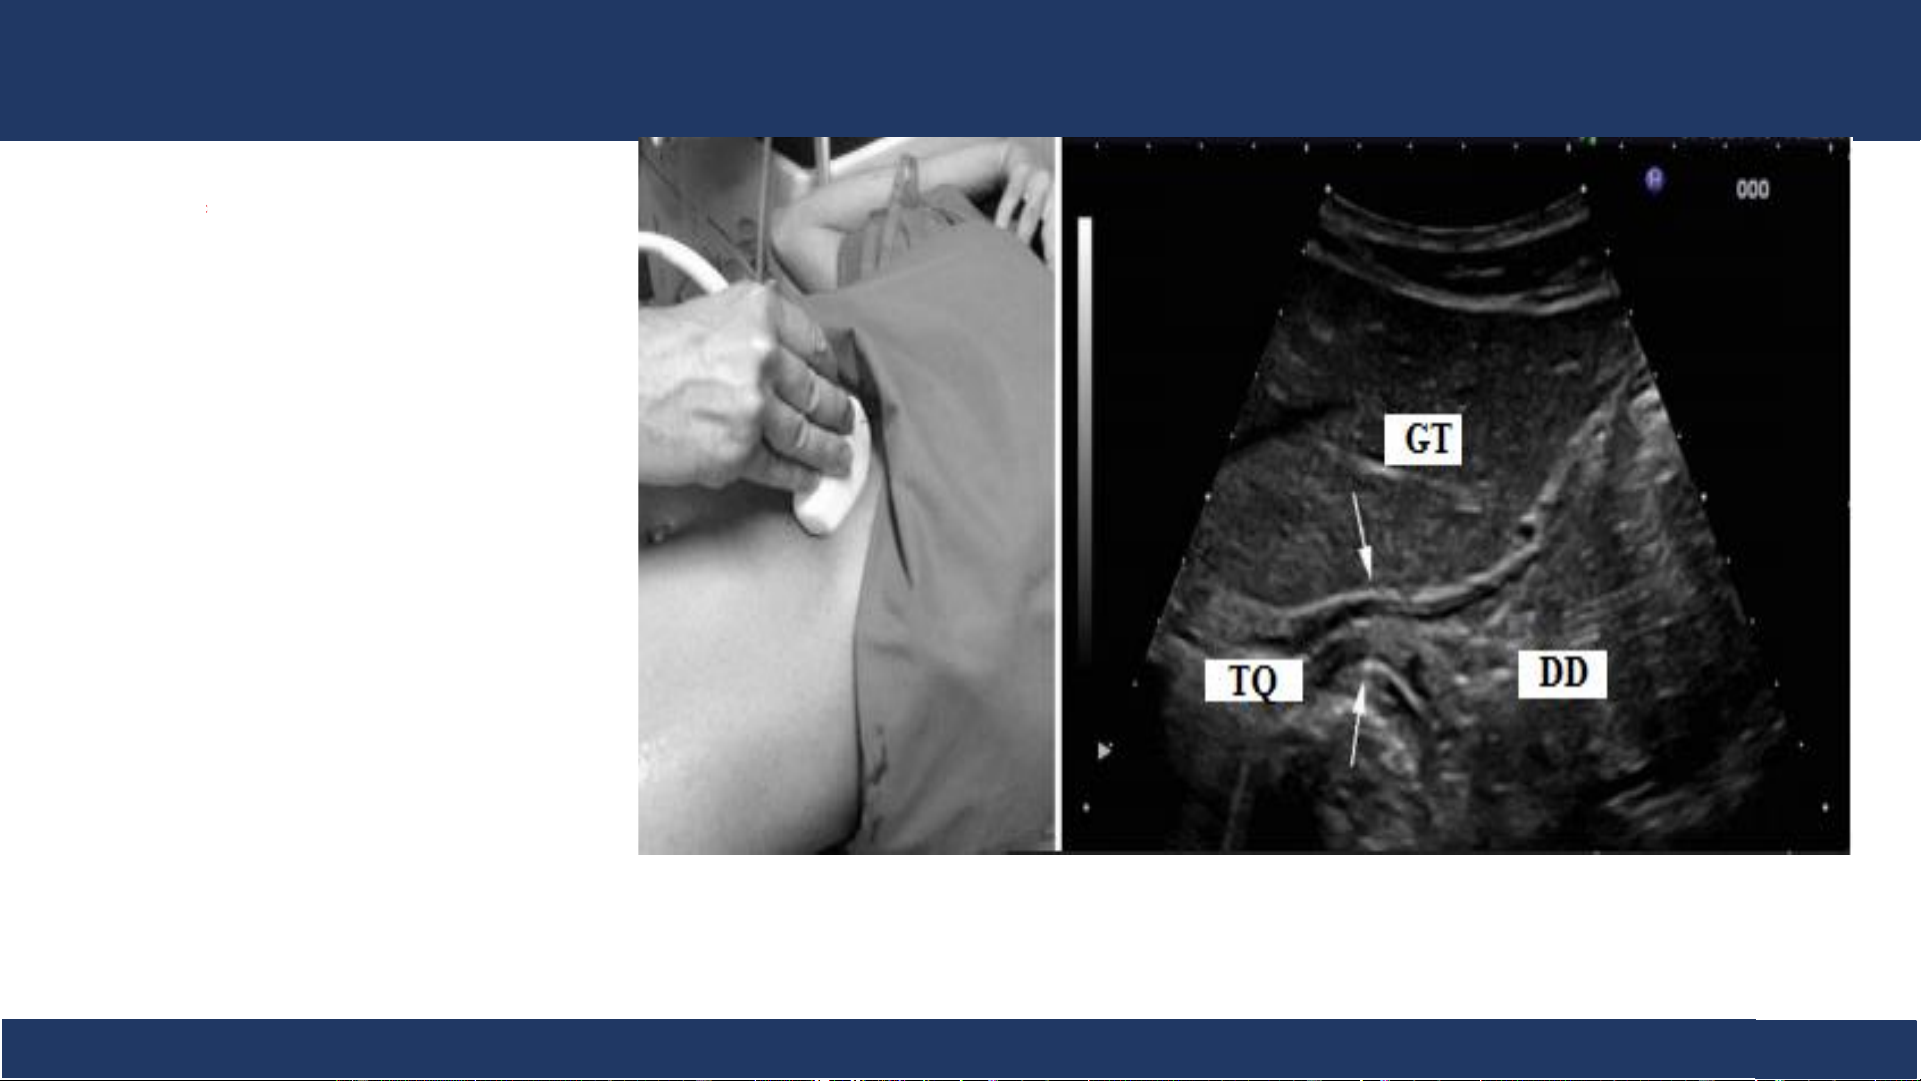

SA: Thực quản - tâm vị .

Thực quản tâm vị: hình

target hay mắt bò ở lỗ tâm vị trên cơ hoành trái,

trước trái cột sống, động mạch chủ bụng và ngay

sau gan trái, phía trên là buồng tim.

Siêu âm mặt cắt dưới

sườn – mũi kiếm xương Thực quản đoạn cuối - tâm vị (mũi tên)

ức chếch lên phía trên Bệnh v B iệ ộ môn n Nh Chẩ i Đồng n đoán 1